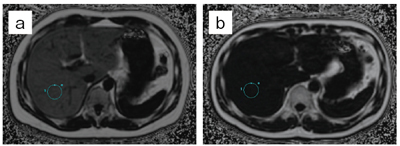

被検体ごとの最適なRF送信を行うため,B1 mapを作成する際にBloch-Siegert shiftを採用している。従来の方法などでは,T1値の影響を受けやすいため,TRを延長しないとその影響を除くことができず,B1 mapの撮像時間が延長してしまっていた。一方で,Bloch-Siegert shiftを用いたB1 mapは,原理的にT1値の影響を受けにくいため,撮像時間の延長はない。また,この手法では,被検体の形状と体組成の両方を考慮し,より正確なB1 mapの作成が可能である。図3に示すように,従来法と比較すると,より均一なRF送信を行うことが可能になる。Discovery MR750w 3.0Tでは“QD” “Preset” “Optimized”の3つのRF送信モードを有している。Optimizedモードでは,Bloch-Siegert shiftを用いたB1 mapにより,自動的に求められた位相比,振幅比に加えて,さらにマニュアル“RF Drive Settings”で微調整が可能であり,さまざまな状況に対応できるシステムになっている。また,均一性という観点からは,RF均一性はもちろんのこと,静磁場の均一性も必須である。優れた磁場均一(0.27ppm@40cmDSV, typical値)とこのMulti Driveの効果により,図4に示すように均一な脂肪抑制効果,および歪みの少ないhigh b-value DWIが可能となる。

![]() 図3 骨盤領域における比較 a:従来法 b:Multi Drive |